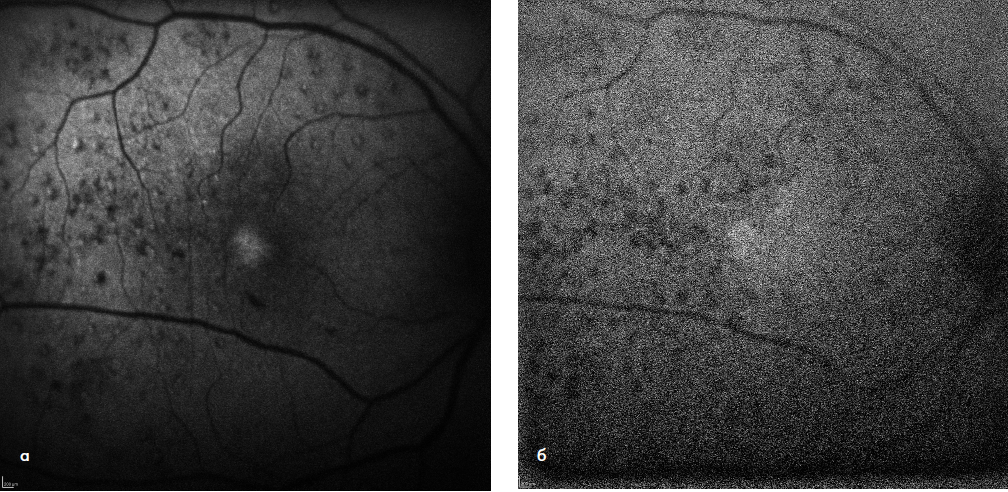

Клиническую оценку безопасности технологии комбинированного лазерного лечения ДМО проводили на основе данных аутофлюоресценции (АФ) в коротковолновом и инфракрасном режимах, а также показателей СЧ по результатам компьютерной микропериметрии. Так, в срок наблюдения 1 месяц было отмечено образование точечных очагов лазериндуцированного повреждения слоя РПЭ (гипер-АФ) в участках, соответствующих зонам порогового лазерного воздействия. В фовеальной аваскулярной зоне, где проводилось только СМЛВ, подобных изменений выявлено не было (рис. 1 а, б). При сравнении АФ-картины в динамике признаков дополнительного повреждения слоя РПЭ в результате повторных сеансов СМЛВ не было выявлено ни в одном из случаев (рис. 2 а, б). По данным компьютерной микропериметрии, в течение всего срока наблюдения образования абсолютных скотом в зонах лазерного воздействия также не наблюдалось во всех случаях (рис. 3 а, б).

Рис. 2. АФ-картина глазного дна той же пациентки в срок 12 месяцев в коротковолновом (а) и инфракрасном (б) режимах. Проведено 2 дополнительных сеанса СМЛВ по всей зоне ретинального отека, увеличения степени лазериндуцированного повреждения не выявлено.

Рис. 3. Компьютерная микропериметрия до лечения (а) и через 12 месяцев после комбинированного лазерного воздействия (б). Образования абсолютных скотом в центральном поле зрения не выявлено.